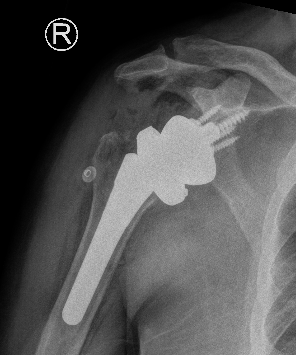

Revision shoulder arthroplasty

Humeral component

Retroversion

- systematic review of humeral version in rTSA

- 14 studies and 1200 patients

- < or > 20°

- at or > 20° of retroversion associated with better clinical outcomes and ROM

Fixation

Depuy Synthes Delta Xtend

Australian Joint Registry 2024

| Fixation | 1 year | 5 year | 10 year | 14 year |

|---|---|---|---|---|

| Uncemented (n=21,000) | 1.9 | 3.5 | 5.1 | 6.9 |

| Hybrid (humerus cemented) (n=2,600) | 1.9 | 3.1 | 4.5 | 4.9 |

Stem length

| Stem length | 1 year | 5 year | 10 year | 14 year |

| Short <100mm (n=10,000) | 2.0 | 3.3 | 4.3 | 5.7 |

| Conventional > 100mm (n=13,500) | 1.8 | 3.6 | 5.4 | 7.3 |